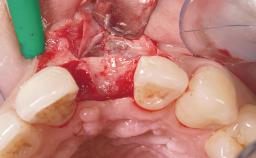

Immediate Placement of an Implant in a Maxillary Left Central Incisor Site

A 33-year-old female patient presented with an upper left central incisor that required extraction after a failed endodontic therapy. The tooth had been traumatized when the patient was a teenager and had undergone several endodontic treatments, including two apicectomy procedures. The patient was in good health and did not smoke. Clinical examination showed that the patient had a high lip line. In full smile, the gingival margins of the upper teeth were visible to the first molars. The gingival margins of central incisors 11 and 21 were only just showing. Examination of tooth 21 confirmed that the tooth was mobile and had hypererupted by 1 mm.

Soft Tissue Grafting Simultaneous

Socket Integrity Damage to one or more bone walls

Bone Volume Damage to one or more socket walls

Soft Tissue Contour and Volume Slightly compromised